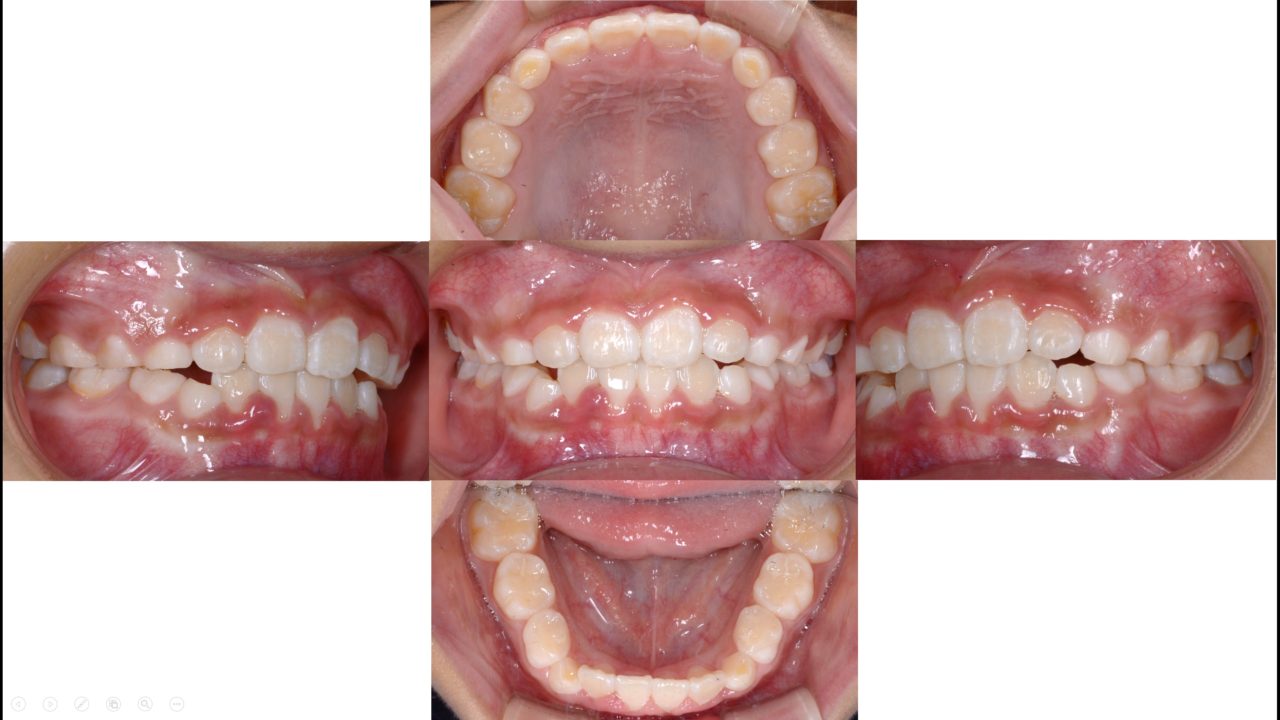

第1期治療終了 2020.8.14

前歯が正常咬合であり、叢生がない状態を確立した。今後はメインテナンスで側方歯永久歯の萌出を管理する